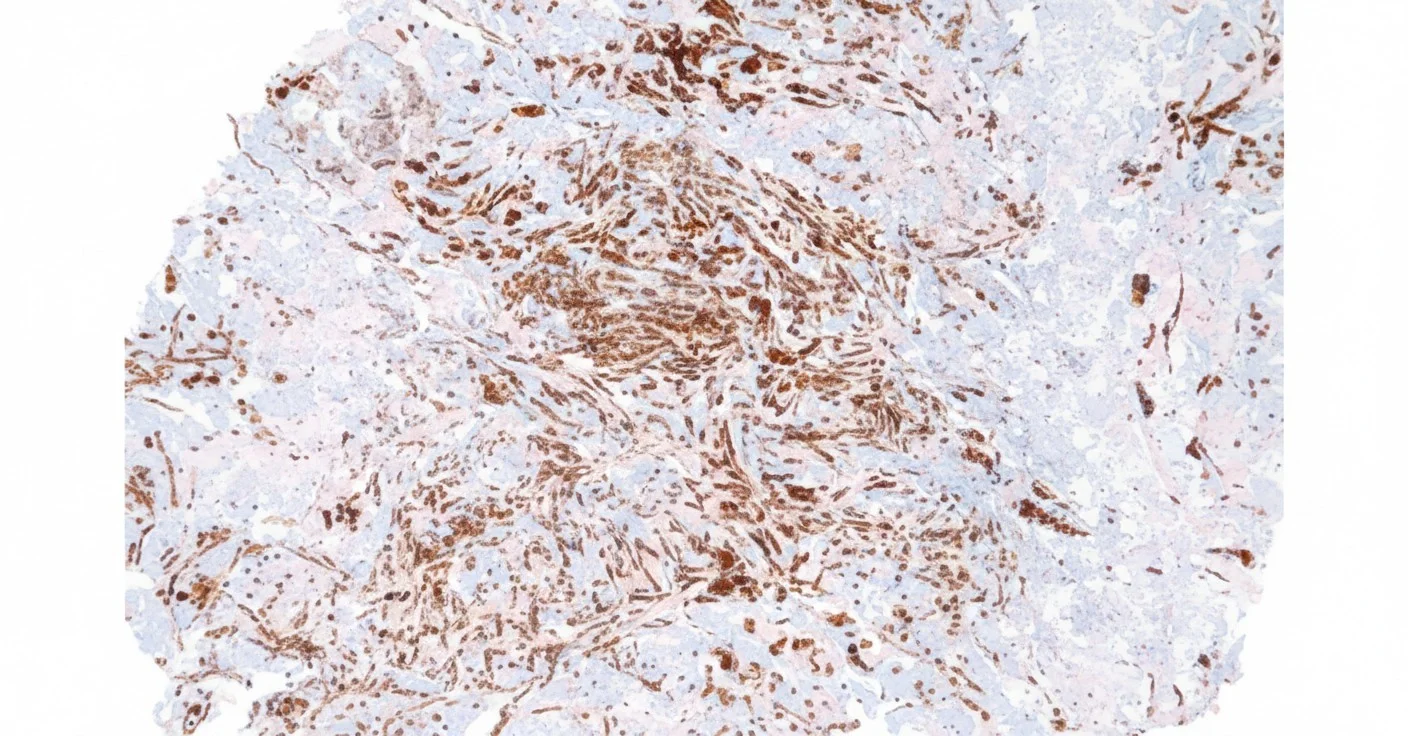

Our AI algorithms perform whole-slide analysis to automatically calculate the percentage of positive cells, distinguish tumor cells from stromal cells, and reduce variability in manual counting.

Precision Cellular Analytics

Proprietary segmentation algorithm achieves sub-micron precision (Dice>0.95 for nucleus/membrane/cytosol). AI enhancement boosts SNR by 10dB, with signal intensity histograms demonstrating raw vs. processed data comparison.

Dice coefficient >0.95 for accurate cell boundary detection and segmentation.

AI-Powered Cellular Segmentation

Sub-micron precision in identifying nucleus, membrane, and cytosol structures with Dice coefficient >0.95